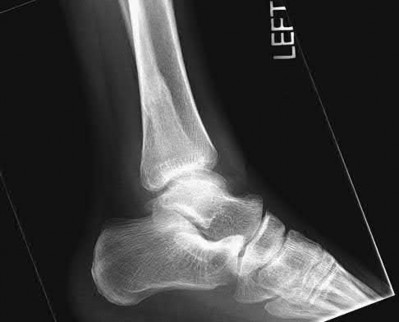

Figure A is an AP radiograph of a posterior knee dislocation. Figure B is a lateral showing the same injury.